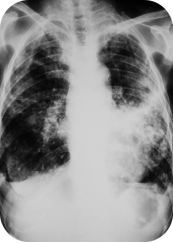

5月前,呼吸与危重症医学科收治了一位青年男性患者,20天前可疑受凉后出现一过性畏寒、发热,之后反复咳嗽,咳少许白色粘液痰,症状持续20+天;院外口服了各种消炎药、止咳药,没啥效果。

以上是他的胸部CT影像,主要表现为左下肺炎症,片絮影+磨玻璃影。